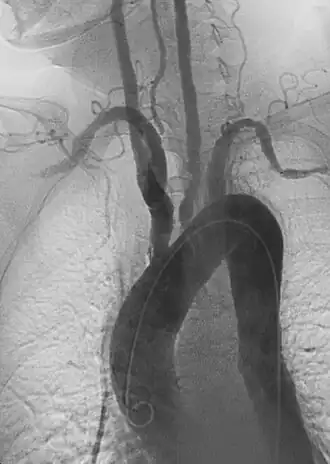

ангиография артериита Такаясу

Расслоения могут возникнуть практически в любой другой артерии. Например, расслоение сонной артерии повышает риск инсульта у пациентов и может распространиться дальше на кровеносные сосуды головного мозга. Расслоение позвоночной артерии встречается реже, но также опасно по тем же причинам. Расслоение брыжеечной артерии может ограничить кровоснабжение кишечника. Расслоение почечной артерии может привести к снижению притока крови к почкам и способствовать гипертонии.[39] Расслоения периферических артерий могут наблюдаться и в других местах рук и ног. Эти расслоения могут возникать в основном из-за очаговых травм, сопутствующих сосудистых заболеваний или как продолжение более крупного, сложного расслоения аорты, которое далее проникает в эти более мелкие ветви.